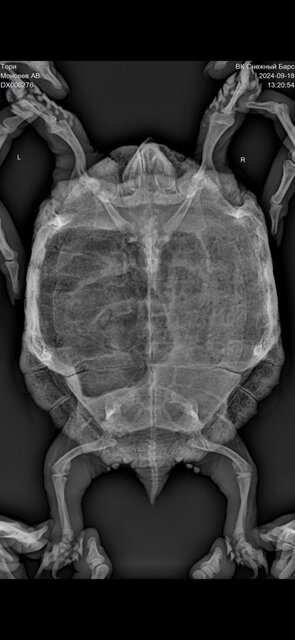

Сделали рентген, я не понимаю, но кажется что, что-то не так с легкими

Посмотрите пожалуйста

9). Рентген в дорсовентральной проекции с вытянутыми конечностями. Для исключения суставной подагры в виду отёков на суставах задних конечностей и патологий в костных структурах.